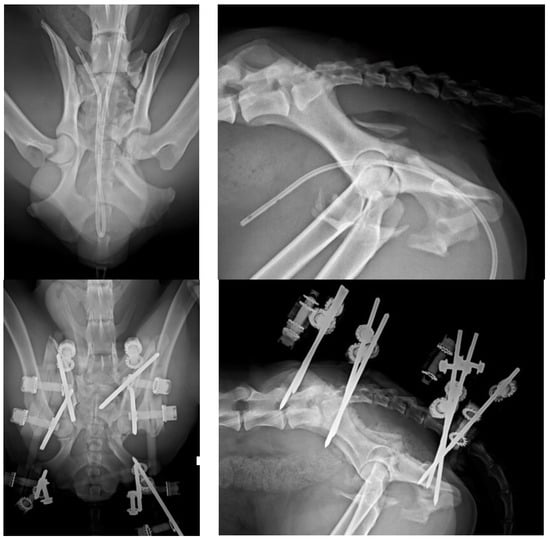

Figure 4. (Top left): Ventrodorsal (VD) projection of a patient with a fracture of the left ilium and a conminuted fracture of the contralateral acetabulum. (Top right): lateral projection of the same patient. (Bottom left): The fractures were reduced and stabilized by a type O radiolucent EF system. Note the plate used for the fracture of the ilium. (Bottom right): lateral projection of the same patient.

There are few studies in the literature addressing EF applied to pelvic fractures in small animals [5], in opposition to human medicine, where its use is common in unstable pelvic fractures, especially in the early stages of treatment [13,14], due to its known biomechanical properties and its peculiar characteristics [15,16,17,18,19]. The modularity of the system and its simple application, either as a temporary or definitive method for fracture resolution, provides speed as a surgical technique, i.e., offering notable advantages in critical patients [20]. These fixators can be radiolucent, thus greatly facilitating the evaluation of healing [21]. Radiographic rechecks are easier, avoiding the need for oblique projections as usual with standard metallic EF frames (Figure 4 and Figure 5). In addition, in patients treated with fluoroscopic-assisted techniques, the interference during the procedure is considerably reduced, allowing reduction maneuvers to be performed much more easily. However, a clear downside of the use of fluoroscopy is the radiation exposure, which may be considerable in long surgical procedures. Nevertheless, in our opinion, a highly experienced surgeon can reduce considerably the amount of radiation needed.